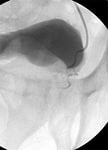

- Трансректальное ультразвуковое исследование предстательной железы (ТРУЗИ)

- Урофлоуметрия (позволяет оценить скорость потока мочи).